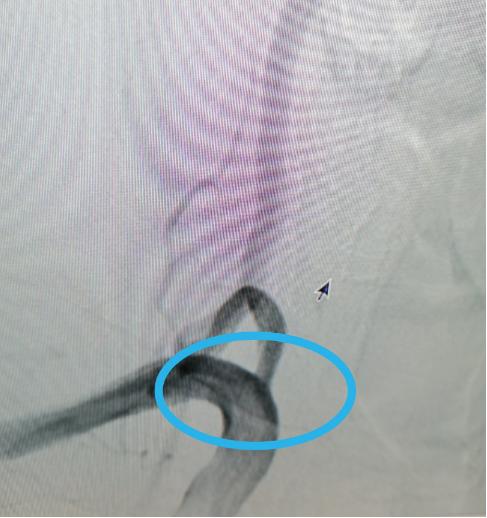

术后↑:支架植入后,狭窄缓解,造影显示椎动脉通畅